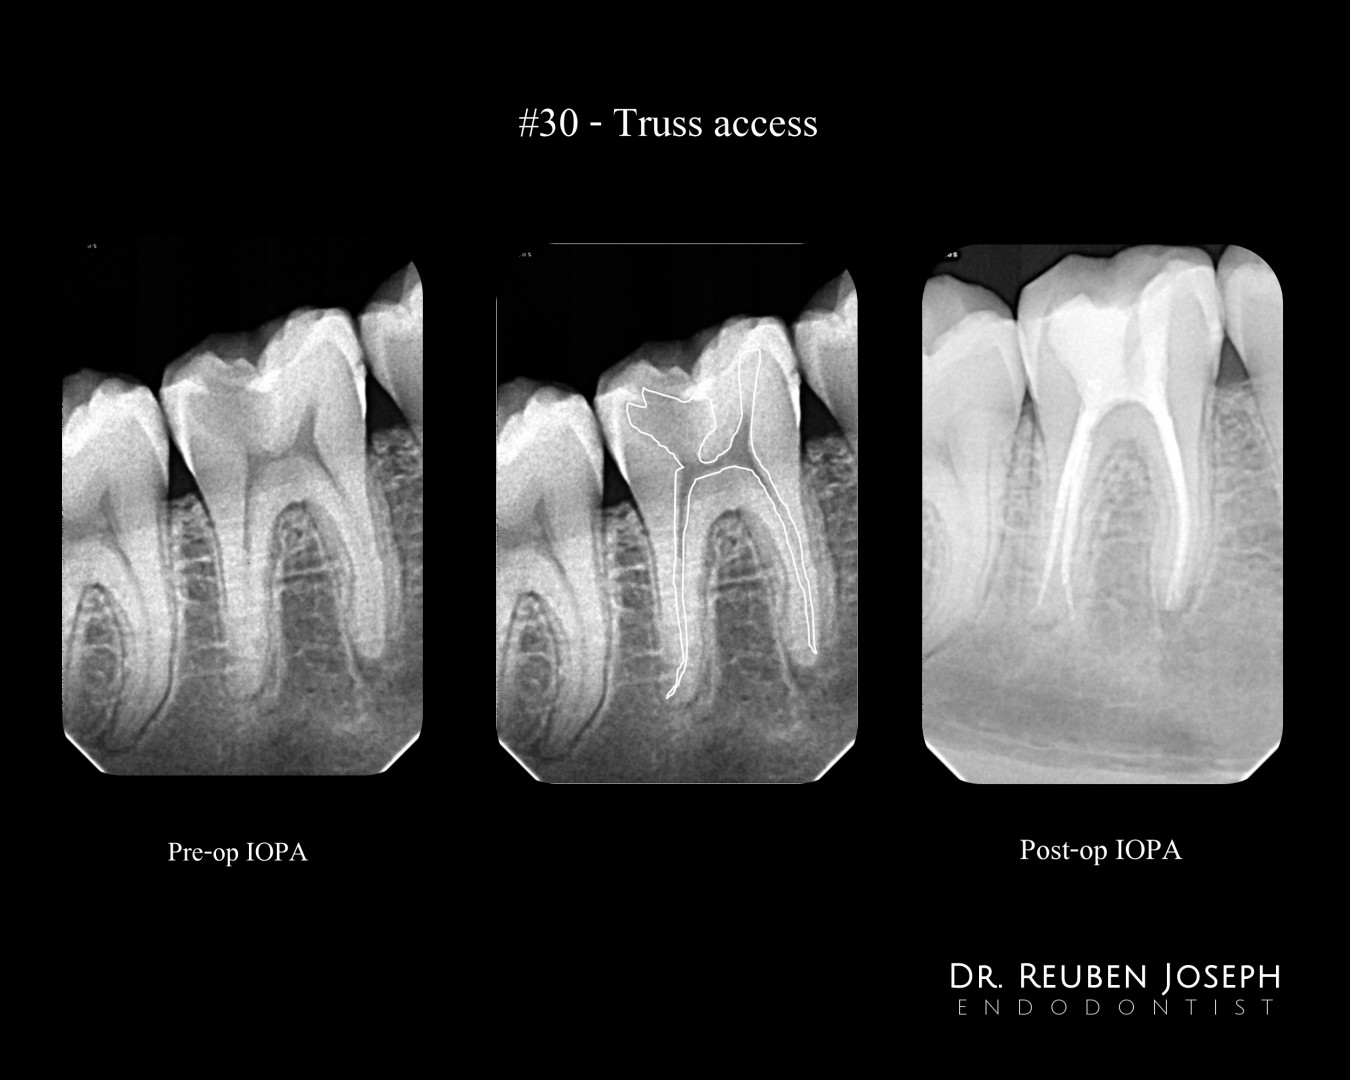

#30 – Truss Access

Pre-op IOPA reveals a #30 with irreversible pulpitis involving the distal pulp horn and a fairly intact Mesio-occlusal surface.

Treatment plan: Truss access planned leaving the bridge of dentin in the centre intact. Truss access’s are precise and more conservative with a CBCT. But in a scenario where a CBCT is not feasible for routine cases, a good pre-op IOPA assessment and tracing the caries outline can help limit the extensions. I call it the Desi-IGE

Well managed! Without a CBCT a good bitewing is critical for direct dentin conservation. I would rather have a good BW rad than a PA rad for RCT.